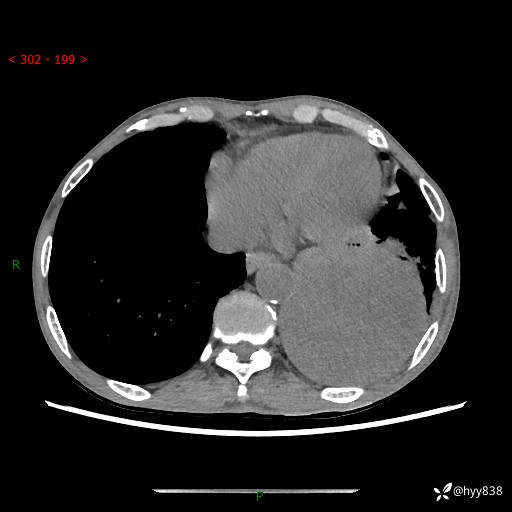

77岁/男,腹痛2月,CT发现左肺占位1天。巨大肿块,肺内或肺外来源…结果公布~

主诉:腹痛2月,CT发现左肺占位1天

现病史:患者于2025年9月间断左下腹胀痛,在当地镇卫生院行彩超检查考虑泌尿系结石,行止痛排石对症治疗未见明显好转;1天前腹痛症状加重,至当地市第三人民医院行CT检查:左肺下叶巨大团块状软组织影,考虑肿瘤性病变,建议增强CT检查;左侧胸腔积液;纵膈内淋巴结肿大;双肺肺气肿;右肺中叶纤维灶。为进一步求治,来我院就诊。

胸部CT平扫+增强